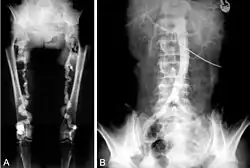

Die Mediasklerose findet sich als röhrenförmige Verkalkung von Arterien gelegentlich als Nebenbefund bei radiologischen Untersuchungen des Skelettsystems.[1][2] Sind entsprechende Grunderkrankungen bei einem Patienten bislang unbekannt, kann ein derartiger Befund Anlass sein, danach zu fahnden. Angiographisch zeigen sich bei der Mediasklerose offene Gefäße ohne nennenswerte Schwankungen des Innendurchmessers. Typischerweise ist der mittels Dopplersonographie an den Knöcheln gemessene Blutdruck mindestens 1½ mal so hoch wie am Handgelenk (Knöchel-Arm-Index > 1,5).[4]